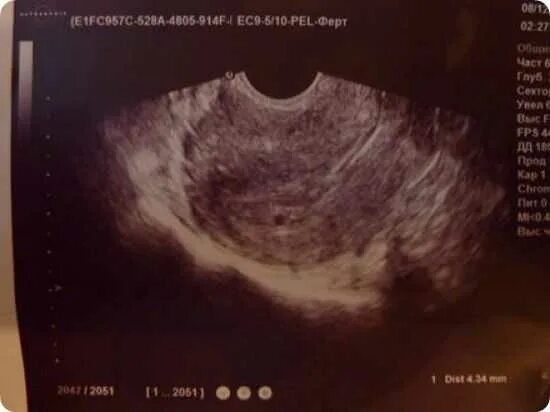

Беременность 4 недели и 2 дня